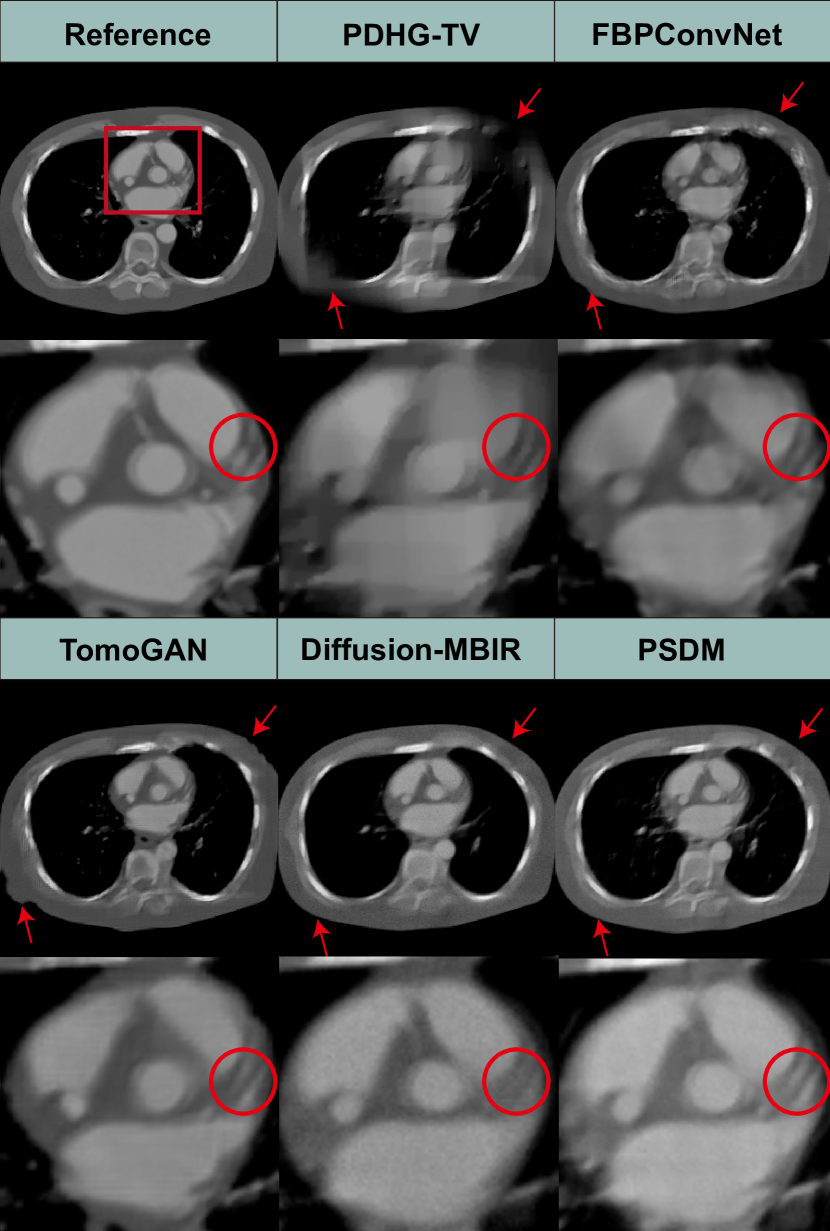

Figure 2: Reconstruction results from the simulated dataset for different methods with a scanning angular range of 120° with Case 1 and Case 2. The 2ndsuperscript2𝑛𝑑2^{nd} and 4thsuperscript4𝑡4^{th} rows show the SSIM map compared to the ground truths. The display window is [540540-540 100010001000] HU.

Fig. 2 shows the representative reconstruction results for patient 153 across phases 100 and 112, utilizing different methods for 120-degree limited-angle reconstruction. The first and third rows display the reconstruction results, while the second and fourth rows provide the corresponding SSIM map for comparative analysis. For the 120-degree condition, most of the methods achieve satisfactory results, except for FBP and PDHG-TV, which are affected by strong limited-angle artifacts.

Refer to caption

Figure 3: Magnified region of interests for different methods with a scanning angular range of 120° for Case 1 and Case 2. The magnified areas are marked in Fig. 2. The display window is [540540-540 100010001000] HU.

FBPConvNet and TomoGAN show compromised edge quality along oblique directions, while the Diffusion-MBIR and PSDM demonstrate superior edge preservation. However, the Diffusion-MBIR images lack the finer details that are perceivable in PSDM images.

For further comparison, two regions of interest (ROIs) are extracted from Cases 1 and Case 2, and subsequently magnified as in Fig. 3. Upon close examination of the structures, specifically those indicated by the red arrows, it is evident that the images are subject to blur and distortion when they are processed by PDHG-TV, FBPConvNet, and TomoGAN. Conversely, the Diffusion-MBIR and PSDM yield superior image quality. However, it should be noted that Diffusion-MBIR images are not entirely devoid of imperfections, as they continue to retain some noise and exhibit minor distortions at the locations indicated by the red arrows. Furthermore, when looking closely at the area indicated by the red circles, PSDM provides clearer reconstruction of the LAD branches compared to Diffusion-MBIR.

We conduct further tests using a 90-degree limited-angle dataset. The results, along with the magnified ROI images, are presented in Fig. 4. We observe that the PDHG-TV method exhibits noticeable limited-angle artifacts. Both FBPConvNet and TomoGAN demonstrate varying degrees of deformation at the diagonal edges. The diffusion-based methods appear to be more stable, without significant evident structural deformation. Similar to the 120 degree limited-angle reconstruction results, our PSDM method outperforms the Diffusion-MBIR in reconstructing finer structural details in LAD area, as highlighted by the red circles.